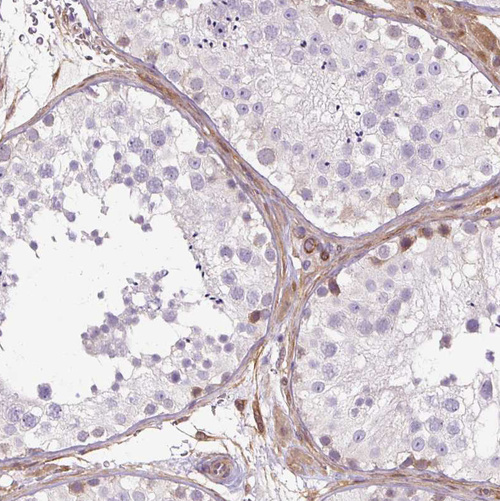

Immunohistochemistry analysis in human placenta and skeletal muscle tissues using HPA051237 antibody. Corresponding CNN3 RNA-seq data are presented for the same tissues.